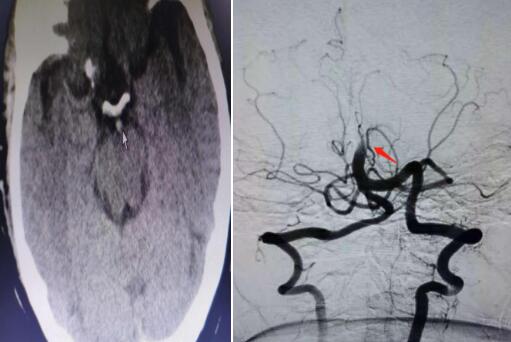

近日,我院脑病科(神经内科)会诊了一名急性脑梗死患者。患者在住院过程中突发头晕头痛、口角发麻,随即转为昏迷状态,瞳孔呈针尖样改变,经急行头颅CT检查排除了脑出血。脑病科副主任杨波及其介入团队接到消息后迅速赶往医院,发现患者头颅CT基底动脉高密度影。综合分析,杨波判断患者是基底动脉发生急性闭塞。

头颅CT上箭头指示基底动脉高密度影,提示基底动脉闭塞,

DSA造影显示为基底动脉尖综合征

导管顺利到位后造影显示确认了杨波的判断:患者为基底动脉完全闭塞,无任何正向血流通过。杨波与介入医师用微导管及导丝配合,小心地一点点通过闭塞的血栓,快速而细致地进行着每一步操作,每一分钟、每一秒钟对于患者都至关重要。闭塞的血管早开通一分钟甚至都会多挽救出更多的脑组织。